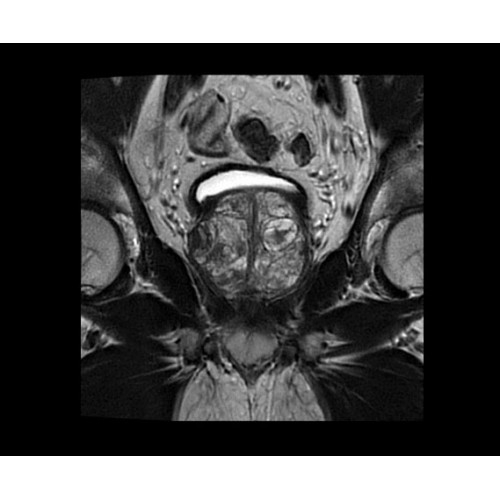

SIGNA PET/MR 3.0T — это гибридная система, в которой совмещаются две принципиально разные технологии — магнитно-резонансную томографию (МРТ) и позитронно-эмиссионную томографию (ПЭТ). Система отличающийся высокой чувствительностью и эффективностью и предназначена для диагностики в области онкологии, неврологии, кардио-васкулярных исследований, исследований воспалительных процессов.

Компания GE Healthcare представляет революционную, полностью интегрированную систему SIGNA PET/MR1, в которой сочетаются времяпролетная технология (TOF) и возможности напряженности магнитного поля 3.0 Тл. Мы поможем вам поднять исследования на более высокий уровень. SIGNA PET/MR позволяет достичь впечатляющей точности и скорости исследований, а благодаря новейшей технологии реконструкции Q.Clear2 качество изображений улучшается в два раза. Кроме того, в систему включен полный набор клинических приложений и гибких катушек для проведения любых видов исследования, открывая для вас возможности визуализации, о которых вы даже не догадывались.

В систему SIGNA PET/MR встроены запатентованные детекторы кремниевого фотоумножителя (SiPM) и сверхчувствительные кристаллические сцинтилляторы на основе лютеция толщиной 25 мм. Благодаря этому обеспечивается исключительная чувствительность и возможность использования времяпролетной диагностики (TOF).

Кроме того, в результате использования технологии TOF и инновационной технологии реконструкции Q.Clear вы сможете добиться прекрасного соотношения сигнал/шум. А благодаря технологии нулевого времени эхо (ZTE) визуализировать костную структуру без ионизирующего излучения. Все эти разработки для улучшения качества сканирования и точности анализа помогут вам использовать весь потенциал ПЭТ/МРТ.

Впечатляющие клинические возможности

Система SIGNA PET/MR предлагает впечатляющие клинические возможности и открывает доступ к наиболее полным пакетам программных приложений.